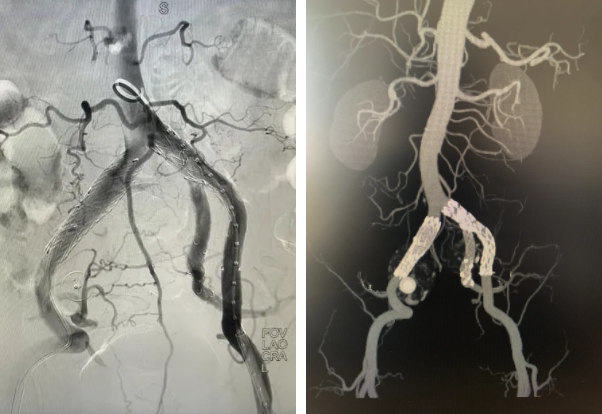

心脏问题解决后,治疗的“接力棒”交到了血管外科团队手中。团队预先在腹主动脉支架上为副肾动脉开窗并标记,随后在术中精准定位,将导丝导管通过开窗口超选入副肾动脉并成功植入支架,最终造影显示,腹主动脉瘤被完全隔绝,副肾动脉血流通畅,且无内漏。术后,患者肾功能维持良好,平安出院。

患者术前、术后DSA检查结果对比